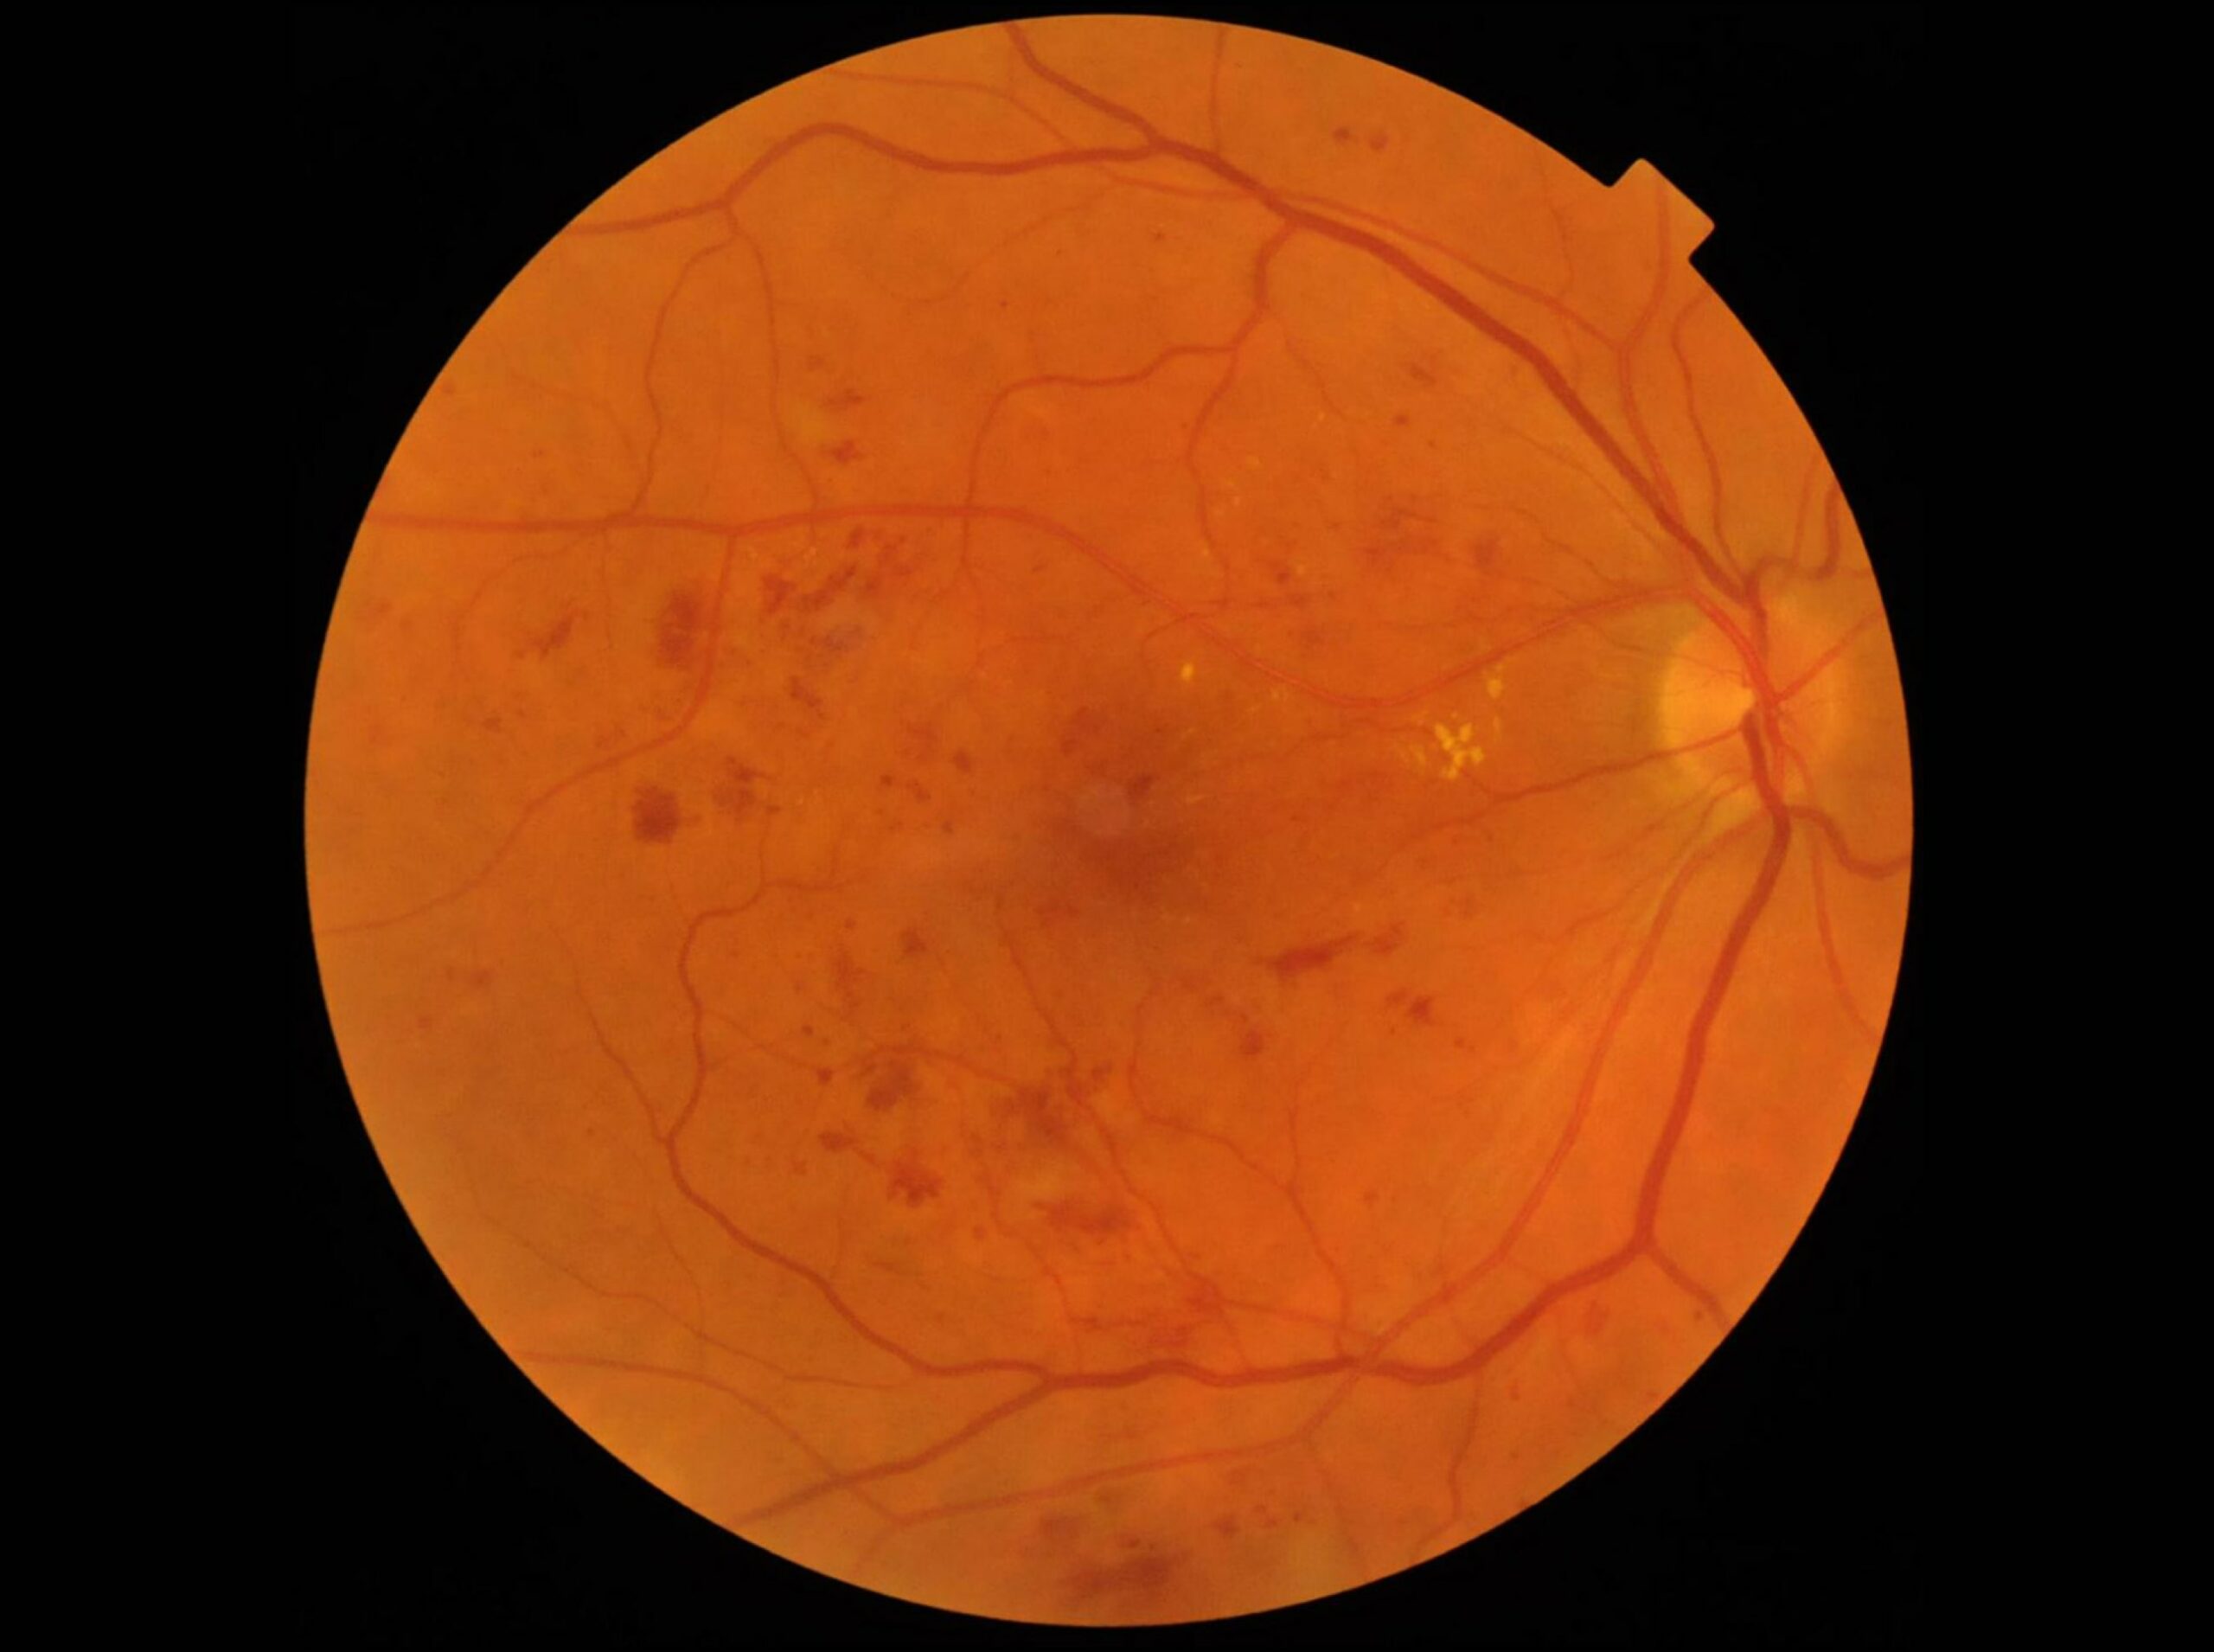

Le Fond d’œil

L’examen de dépistage de référence reste le fond d’œil, réalisé après dilatation de la pupille. Le fond d’œil est utile pour rechercher des signes caractéristiques de la rétinopathie diabétique : hémorragies rétiniennes, exsudats lipidiques, œdème maculaire, micro-anévrismes ou néovaisseaux, et nodules cotonneux (petites zones blanches d’infarctus localisé de la rétine interne). La quantification de ces signes permettra de déterminer le stade de la maladie.